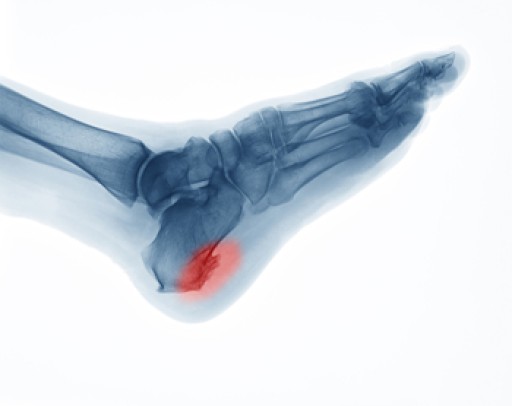

Why Do Heel Spurs Occur?

Heel spurs can occur when foot muscles and ligaments are strained, the plantar fascia is overly stretched, or the membrane covering the heel is repeatedly torn. In response to this trauma, the body sends calcium to protect and strengthen the area, which can build up over a period of time and cause bony projections on the bottom of the heel bone towards the arch, at the back of the heel, or beneath the arch. While some heel spurs go undetected, many people experience tenderness and pain in the heel, especially when walking barefoot on surfaces that are hard. If you have heel pain, a podiatrist can examine you and use X-rays to help determine if a heel spur is present, and prescribe treatments such as orthotics, exercise, injections, or even surgery to provide relief.

Heel spurs are formed by calcium deposits on the back of the foot where the heel is. This can also be caused by small fragments of bone breaking off one section of the foot, attaching onto the back of the foot. Heel spurs can also be bone growth on the back of the foot and may grow in the direction of the arch of the foot.